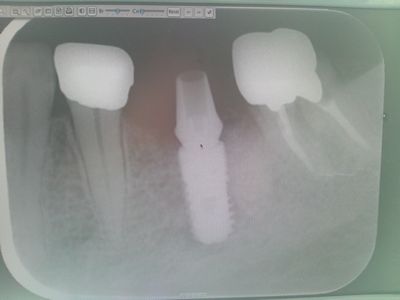

インプラントの埋め込み施術が終わり、早2ヶ月。

骨が形成された頃ということで歯医者に行って来ました。

そこで、びっくりなことが。

歯茎を開いて、土台を作るためにインプラントに杭を打ち込むのですが・・

骨の形成がよくて、インプラントを食い込んでしまった模様・・・。

そこで、再度、骨を砕くのですが・・大変そうでした。

周りの骨を砕いたので、本日、歯の型をとれず、仮土台をつけたのみ。

それがこんな感じ。

ブリッジのためのけずられ王冠を付けられた、左の歯(前側) 虫歯の王冠(奥歯)

はっきり分かります。   神経に薬が入っているか否か。

白いのは薬のためで、これで神経は死んでいます。

「歯茎を切ったので痛みますよ~」と、治療代で飲んだあとに、さらに痛み止めをくれたが、

それがよく効いたのか、痛みはなかった。